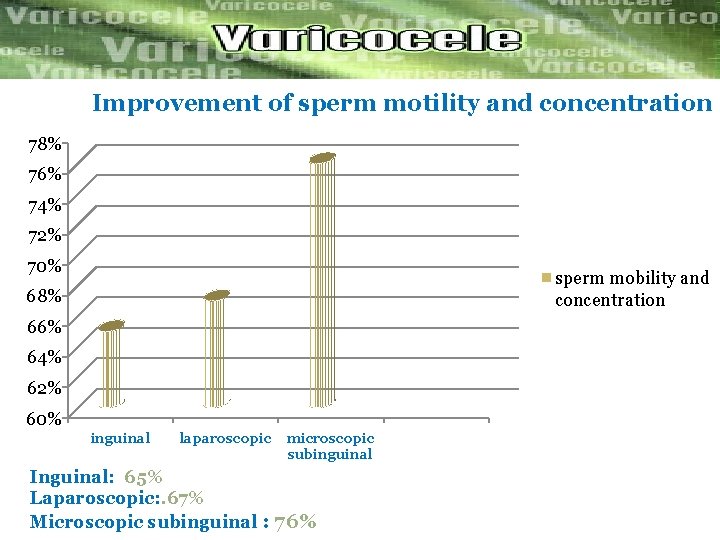

Improvement of sperm motility and concentration 78% 76% 74% 72% 70% sperm mobility and concentration 68% 66% 64% 62% 60% inguinal laparoscopic microscopic subinguinal Inguinal: 65% Laparoscopic: . 67% Microscopic subinguinal : 76%